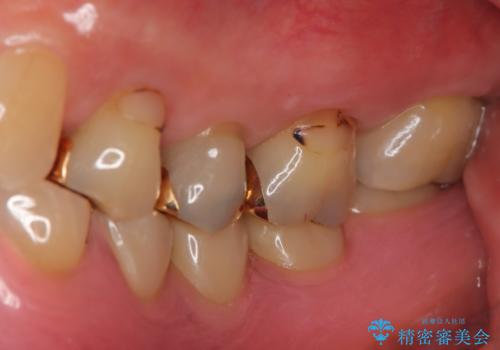

- 定期的に本院に通院されている患者様で、前歯の揺れがあると相談されました。下の奥歯が左右合わせて3本喪失されており、噛み合わせの負担が前歯にも集中していることを説明しました。右下6番の歯に関しては、事前の診査で十分な骨量がありましたのでインプラントを1本埋入しました。左下5番・6番にも本来はインプラントを埋入したかったのですが、骨量が十分でなく、骨を増やす処置をすると神経が近くリスクがあることから、審美性に配慮した金属のばねが見えないノンクラスプデンチャーを製作しました。また、このとき入れ歯を支える左下7番に根尖病変がありましたので、根管治療も行っております。(根管治療は当院院長で専門医を持つDr.林が担当しています。)治療終了後、約1年が経過しましたが、問題なく経過しており患者様も喜ばれていました。